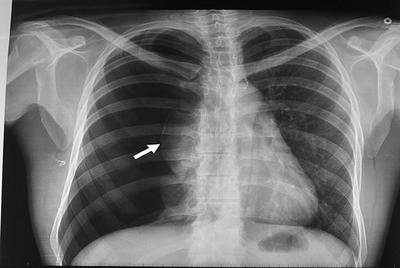

Question

patología que se observa en la radiografía.

Answer

• derrame pleural

• atelectasia

• neumotorax